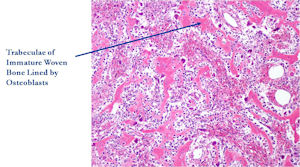

Microscopic Pathology

- Interlacing network of bone trabeculae in a loose fibrovascular stroma

- Prominent vessels

- Osteoblasts are plump, active, scattered mitotic figures

- Osteoblasts line up around periphery of trabeculae (Osteoblastic Rimming)

- Soft tissue component usually surrounded by shell of reactive bone or periosteum (Egg Shell Rim of Calcification)

- No cartilage production (as opposed to osteosarcomas that may contain areas of cartilage)